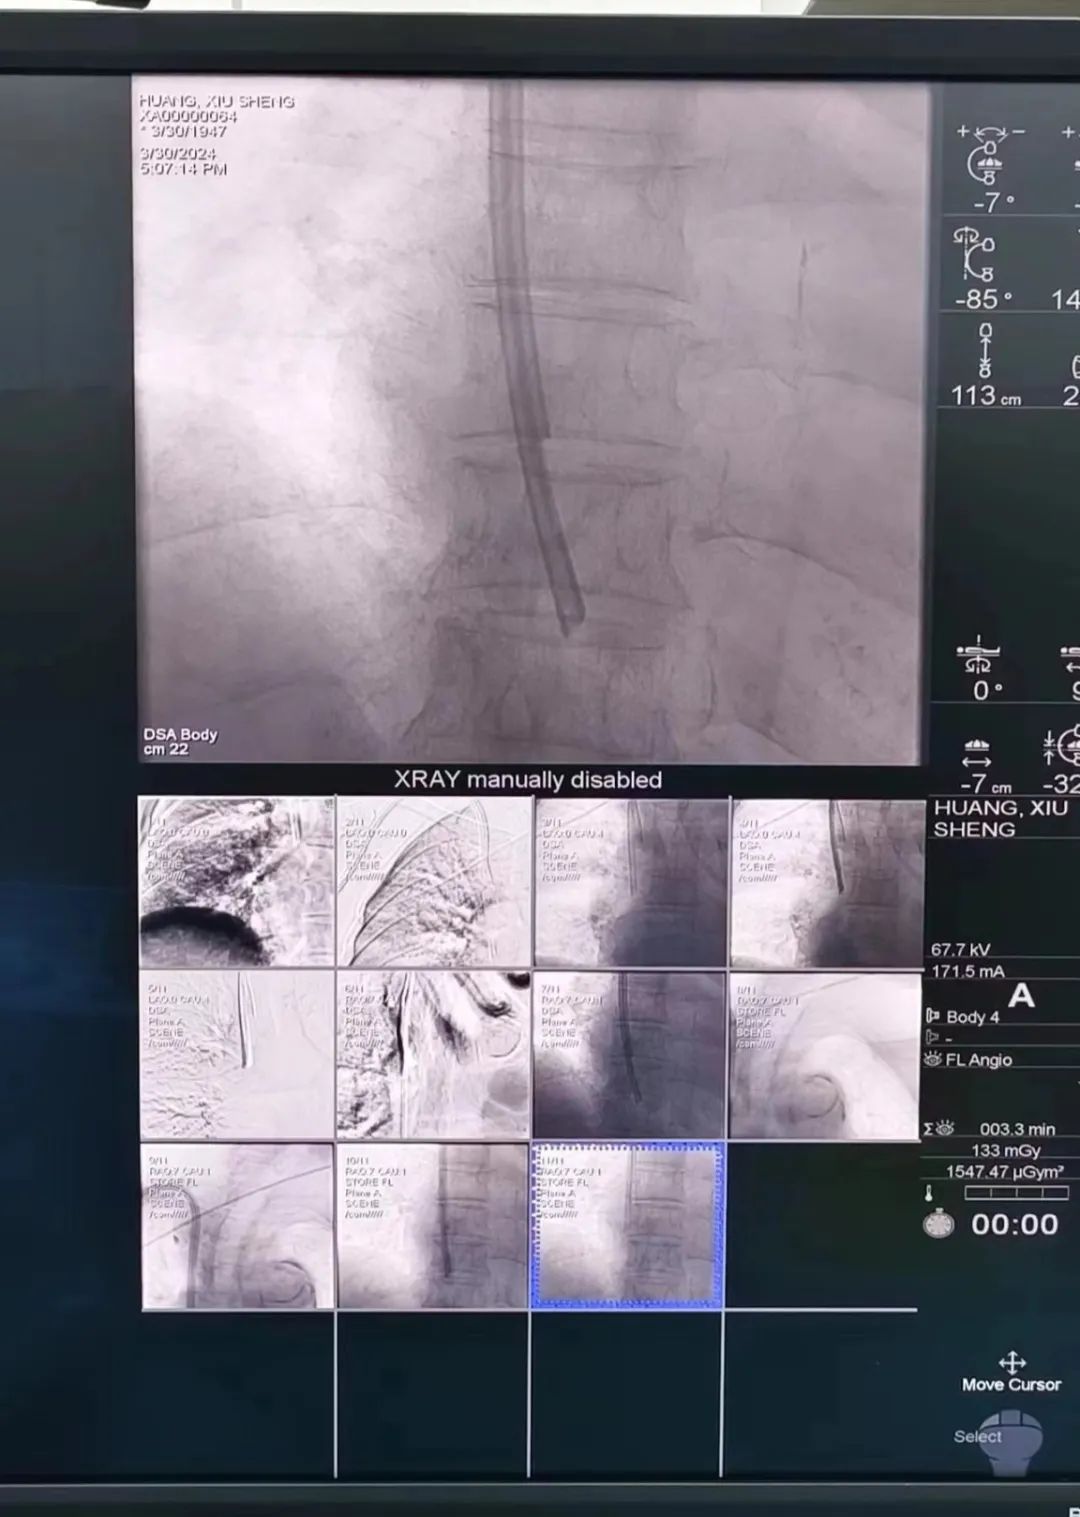

我院肾病科成功开展首例DSA(数字减影血管造影术)下带隧道和涤纶套的透析导管更换术

介入技术也成为该领域的重要保障措施。与传统置管相比,介入下置管更为安全精准及可视化,导丝精准进入,减少血管损伤及防止误入分支静脉,对血管基础较差,血管狭窄等血管条件复杂情况的治疗,具有得天独厚的优势,是未来发展重要方向之一。